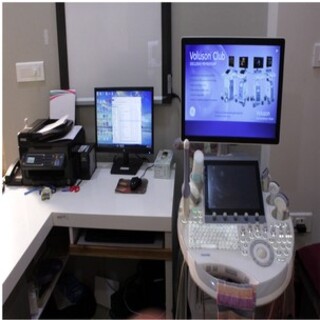

Modern Equipment

We use the first-class medical equipment for timely diagnostics of various diseases.

Modern, imported, high end, state of art machines. (Ultrasound, CT scan, MRI scan, Mammogram, etc.)